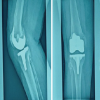

A retrospective analysis was conducted on data from 300 who underwent robotic TKA using a system that incorporates computed tomography (CT)-derived bone models. TEA and PCA were measured preoperatively on CT . Each patient underwent pre-operative CT scans of the ankle, knee, and hip and was instructed to stretch the knee joints as far as feasible. Jplanner software (Java, San Diego, CA) was used to segment all of the scans. A three-dimensional (3D) replica of the patient’s degenerative knee joint was generated by segmenting the femur and tibia bones. The study included patients who required a total knee replacement due to OA in their knees. The study excluded patients with trochlear dysplasia, arthritis with inflammation, and post-traumatic or septic arthritis. To best identify the median sulcus, two lines of reference were drawn across the axial portion of the femur’s distal end, where the femoral epicondyles intersect. The “posterior condylar axis” (line 1) is formed by the posterior areas of both the lateral and medial condyles, whereas (line 2) “the surgical transepicondylar axis” connects the most prominent region of the “lateral epicondyle” to the “medial epicondyle’s median sulcus” (Fig. 1). “The PCA is the angle formed by the surgical TEA and the posterior condylar line” (Fig. 2a and b, Fig. 3) depicts “the surgical TEA (surg TEA) [9], the anatomic TEA (anat TEA) [10], and the angle between them.”